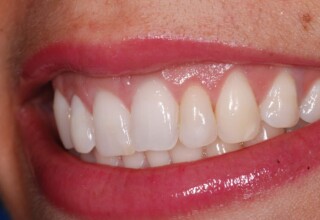

Όψεις Σύνθετης Ρητίνης

Οι όψεις ρητίνης προσφέρουν έναν οικονομικό τρόπο αισθητικής βελτίωσης της εμφάνισης των προσθίων δοντιών ενίοτε και των προγομφίων. Οι δυνατότητες τους πολλές, μπορούν να κάνουν και θαύματα! Ο μονός περιορισμός η κλινική ευχέρεια και η φαντασία του επεμβαίνοντος. Σε αυτήν την ασθενή οι τέσσερεις άνω τομείς είχαν ο καθένας το δικό του πρόβλημα(δυσχρωμία, απόκλιση) και επιπλέον: διαστήματα, πολλαπλές αποχρώσεις, κακή σχέση μεταξύ τους και με τα ούλα. Αποκαταστάθηκαν με τέσσερεις άμεσες όψεις ρητίνης (η μια πάνω σε στεφάνη πορσελάνης εμφυτεύματος!!!) οι οποίες κατασκευάστηκαν ενδοστοματικά!